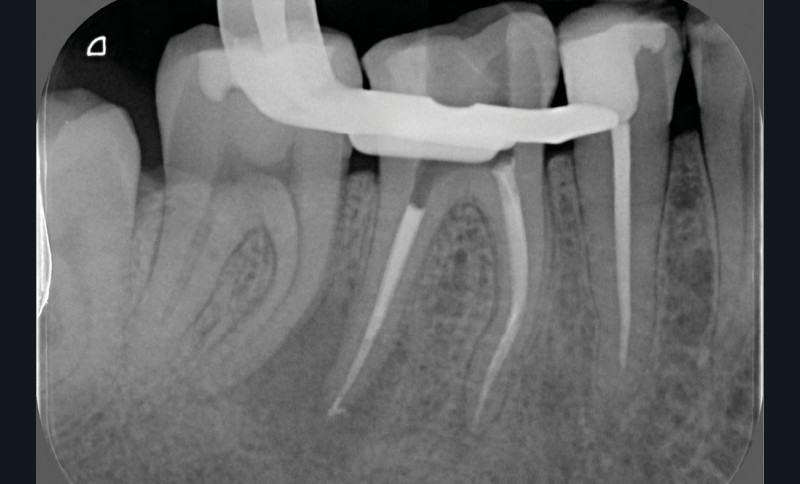

La préparation mécanique est principalement réalisée à l’aide d’instruments NiTi utilisés en rotation continue ou en réciprocité selon une approche corono-apicale. La mise en forme est ainsi plus rapide et respecte mieux le trajet canalaire initial qu’avec une instrumentation manuelle. Le diamètre apical et la conicité de la préparation canalaire font toujours débat. Ils dépendent de l’anatomie initiale et doivent permettre une irrigation efficace sans fragiliser la dent. Ainsi, un diamètre apical de 30 et une conicité de 6 % sont souvent proposés comme objectif minimal à atteindre [3] (fig. 1).